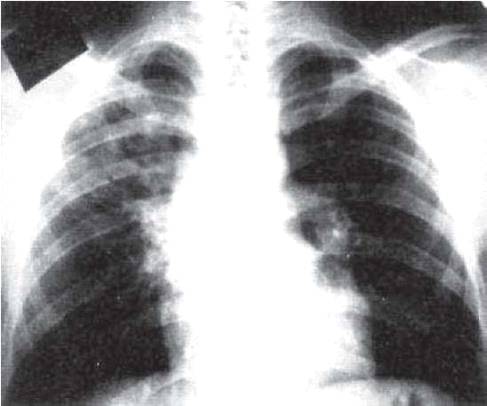

Рис. 11.17. Лобит с поражением верхней доли правого легкого. Рентгенограммы легких в прямой проекции.

Рентгенологическая картина лобарного инфильтрата (лобита) соответствует синдрому распространенного затемнения. Расположение и форма затемнения зависят от того, какая доля легкого поражена.. При поражении верхней доли затемнение локализуется в верхнем легочном поле (рис. 11.17). Границы лобита подчеркнуты уплотненными плевральными листками. В боковой проекции форма затемнения приближается к треугольной.